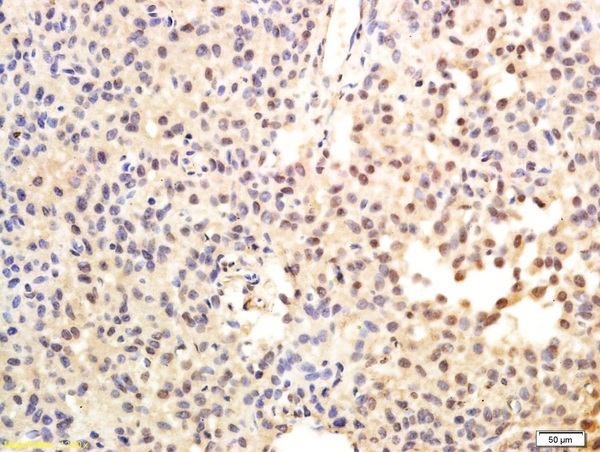

Paraformaldehyde-fixed, paraffin embedded Rat Liver; Antigen retrieval by boiling in sodium citrate buffer (pH6.0) for 15min; Block endogenous peroxidase by 3% hydrogen peroxide for 20 minutes; Blocking buffer (normal goat serum) at 37°C for 30min; Antibody incubation with TERT Polyclonal Antibody, Unconjugated (bs-0233R) at 1:400 overnight at 4°C, DAB staining.